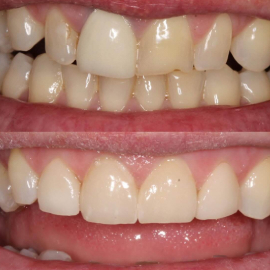

Ceramics can make a smile look nice again